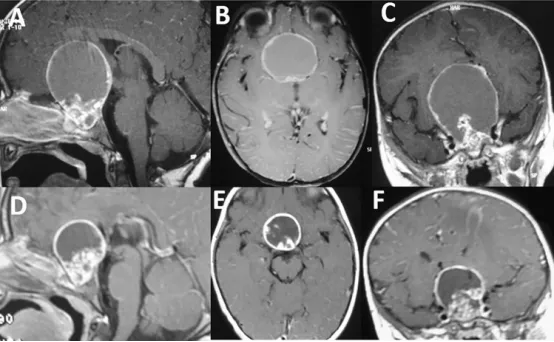

请注意在钆增强T1序列上可见大型强化囊性成分(图A、B、C),其范围延伸至前、中、后颅窝。同时存在明显的双侧脑室积水(图A–E)。在FLAIR序列上,囊液信号较脑脊液为高(图D)。需要注意的是,肿瘤的实质成分仅占一小部分(图E,箭头所示),但其累及Willis环区域(图F,星号所示)。